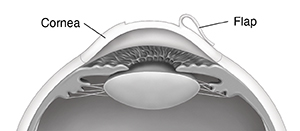

You may feel pressure, but no pain, as your surgeon makes the flap in the top layer of your cornea (epithelium). The flap is folded back but stays attached to the cornea.

The flap is put back into place. The corneal tissue sticks to itself while it heals.